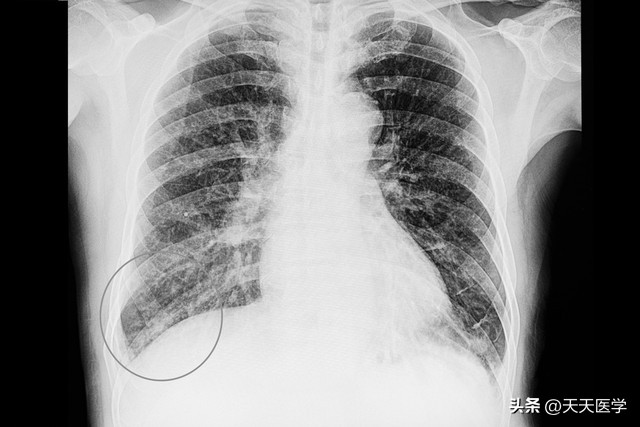

胸部X线检查可见肺纹理增多,磨玻璃状阴影,小片状浸润或广泛浸润、实变,病情严重者显示双肺弥漫性结节性浸润,但大叶实变及胸腔积液者均不多见。病毒性肺炎的致病原不同,其X线征象亦有不同的特征。病毒性肺炎胸部CT表现多样,常见小叶分布的毛玻璃影、小结节病灶,也可表现为网织索条影,支气管,血管束增粗,叶段实变影、可伴有纵隔淋巴结肿大,单侧或双侧少量胸腔积液。病毒性肺炎吸收慢,病程长。